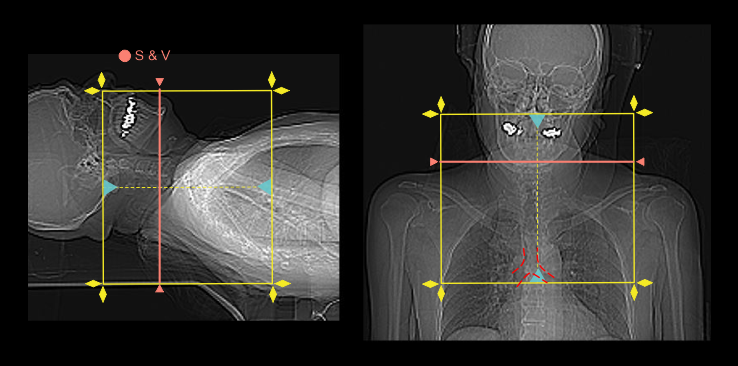

Triggering method or bolus tracking method can be used to initiate the arterial phase because arterial enhancement can be viewed in real-time from the scan and view (S & V), without being delayed to acquire a mixture of arterial and venous enhancements. Additionally, starting the arterial phase in manual is better due to the difficulty of placing a ROI in the small carotid arteries, particularly, in the non-contrast S & V.

- Place the scan and view (S & V) slice at the mid part of the neck.

- Set S & V initiation time to 5 seconds from the contrast injection.

- Plan the scan direction for arterial phase from head to foot.